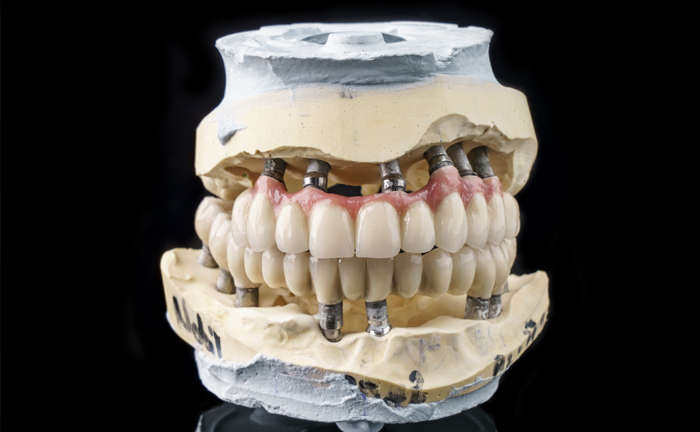

| 4 dental implants |

| 4 abutments |

| 12 temporary teeth (movable) |

| 12 resin crowns (fixed teeth) |

Using the All-On – 4 method; Dental implants are inserted in the same day and in a few hours, a temporary but fixed prosthetic job is performed immediately which will remain until the implants are perfectly integrated into the bone. After about 4-6 months, definitive prosthetic rehabilitation will be performed, which will be screwed onto existing implants. The screw fixing will allow you to remove the restoration (fixed bridge) when necessary.

The specificity of this procedure is that the teeth are fixed on four implants. Thanks to the particular method of inserting the implants, bone reconstruction is not necessary, which is instead a requirement when it is necessary to reconstruct in patients who have total tooth loss.